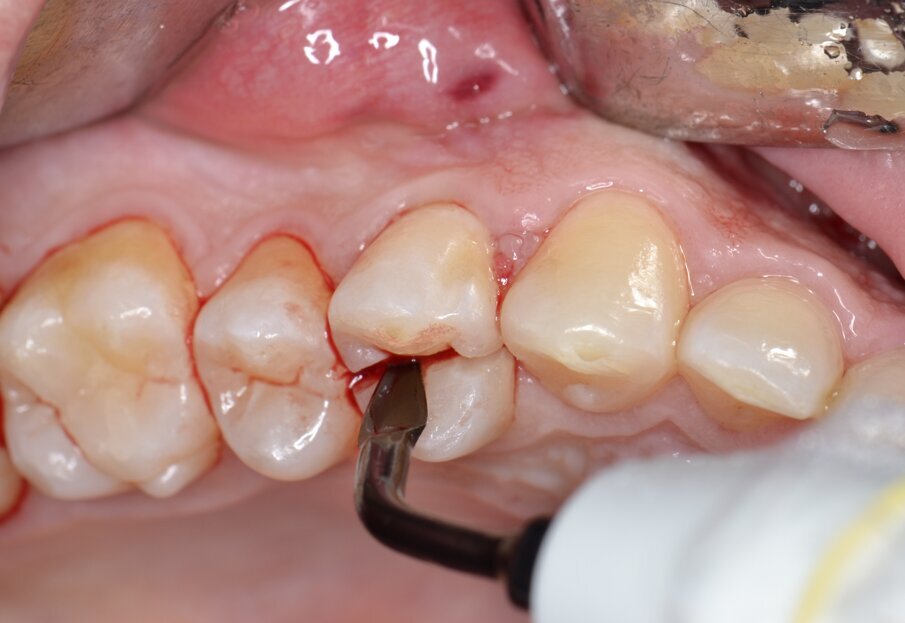

Dopo analgesia locale ottenuta per infiltrazione di Articaina cloridrato 40 mg con epinefrina 1:100.000 la procedura chirurgica ha inizio con l’estrazione dell’elemento fratturato; allo scopo di evitare di danneggiare la parete buccale dell’alveolo e preservare il tessuto osseo residuo per il successivo inserimento implantare, viene praticata un’odontotomia per mezzo di un inserto piezoelettrico dedicato (ES009NT, Esacrom Srl, Imola, Italia) montato su manipolo a ultrasuoni (Esacrom Moto, Esacrom Srl, Imola, Italia) (Fig. 4).

Fig. 4 - Odontotomia mediante inserto ad ultrasuoni.